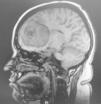

Caso clínicoAnalizamos las alteraciones de conducta causadas por un meningioma orbitofrontal en una mujer de 36 años. Las características clínicas y psicológicas del cuadro son reflejadas.

Case reportWe analyzed the behavioral disturbances caused by an orbitofrontal meningioma in a 36-years-old female. The clinical and psychological features are appointed.